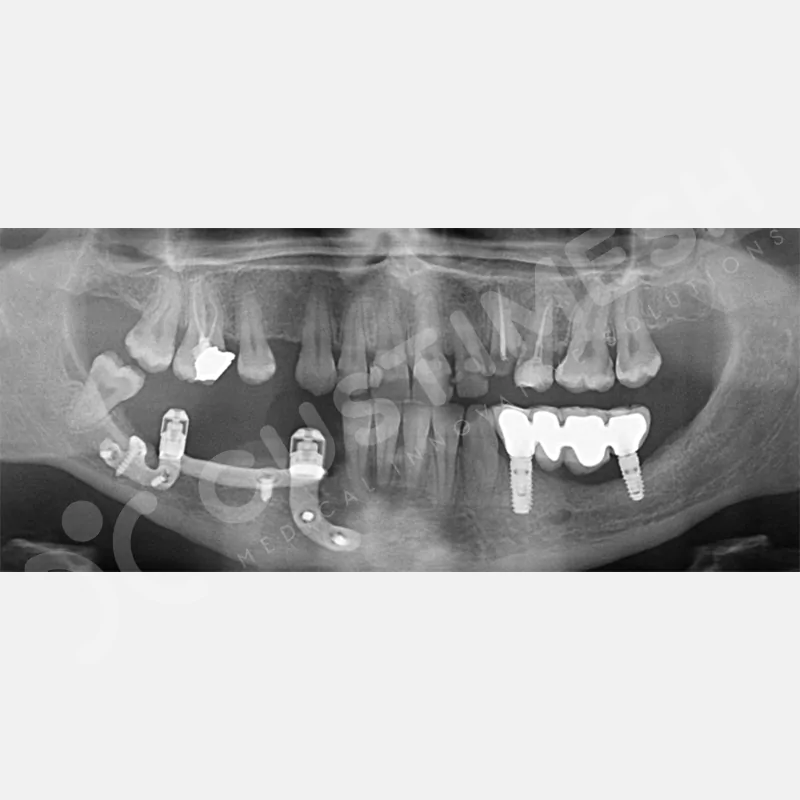

Kişiye Özel Subperiosteal İmplant, çene gelişimini tamamlamamış ve yeterli kemik desteğine sahip olmayan kişilere uygulanan, CAD/CAM teknolojisiyle kişiye özel tasarlanan bir implanttır. Bilgisayarlı tomografi görüntülerinden elde edilen verilerle, bilgisayar destekli tasarım yazılımı kullanılarak geliştirilen bu implant, lazer sinterleme yöntemi ile üretilmektedir

Modern diş hekimliğinde, çene gelişimini tamamlamamış veya ciddi kemik kaybı yaşayan hastalar için kişiye özel titanyum implantlar ile çözüm bulunmaktadır. CAD/CAM teknolojisi ve lazer sinterleme yöntemiyle üretilen bu implantlar, hastanın bireysel anatomik yapısına tam uyum sağlayarak geleneksel implantların uygulanamadığı vakalarda mükemmel bir alternatif oluşturmaktadır. Özellikle ileri derecede kemik kaybı olan hastalar için geliştirilen subperiosteal implantlar, periostun altına yerleştirilerek minimal invaziv bir yaklaşım sunarken, bilgisayarlı tomografi verileri ve sonlu eleman analizleriyle optimize edilmiş tasarımları sayesinde hem estetik hem de fonksiyonel sonuçlar garanti etmektedir. Bu yenilikçi teknoloji, tek seansta implant ve protez uygulamasına imkan vererek hastaların aynı gün doğal gülüşlerine kavuşmalarını sağlarken, kemik greftleme gibi ek işlem ihtiyacını ortadan kaldırarak cerrahi süreci büyük ölçüde kolaylaştırmaktadır. Kişiye özel tasarımı ve üstün biyouyumluluğu sayesinde, daha önce tedavisi mümkün görülmeyen kompleks vakalarda bile başarılı sonuçlar sunan bu implantlar, modern diş hekimliğinde yeni bir çağ açarak hastaların yaşam kalitesini artırmayı hedeflemektedir.

Hekim tarafından onaylanan Custiplate, 3 boyutlu yazıcı teknolojisi kullanılarak Grade 23 (Ti6Al4V) Medikal Titanyum Alaşımından üretilir. - KARGO

VAKA 1

VAKA 2

VAKA 3

VAKA 4